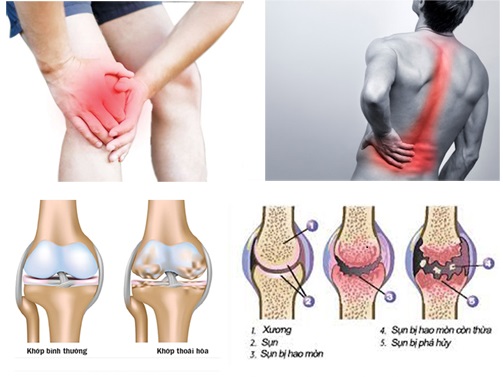

Viêm khớp dạng thấp, loãng xương, một số bệnh khớp khác đều gây ra thoái hóa khớp, làm cho các tổ chức sụn bị hư hỏng, các chất bôi trơn khớp sụt giảm về số lượng, độ nhớt, khớp bị cứng khô gây đau đớn, vận động khớp (đi lại, đứng lên ngồi xuống, lao động) khó khăn, phát ra tiếng kêu lạo xạo. Thuốc điều trị thoái hóa khớp có chức năng tạo ra các tổ chức sụn, hoạt dịch và bảo vệ các tổ chức này. Có nhiều thuốc được nghiên cứu nhưng chỉ có ba chất chính glucosamin, chondroitin, hyaluronat, được FDA, EMA công nhận có đầy đủ các chức năng này.